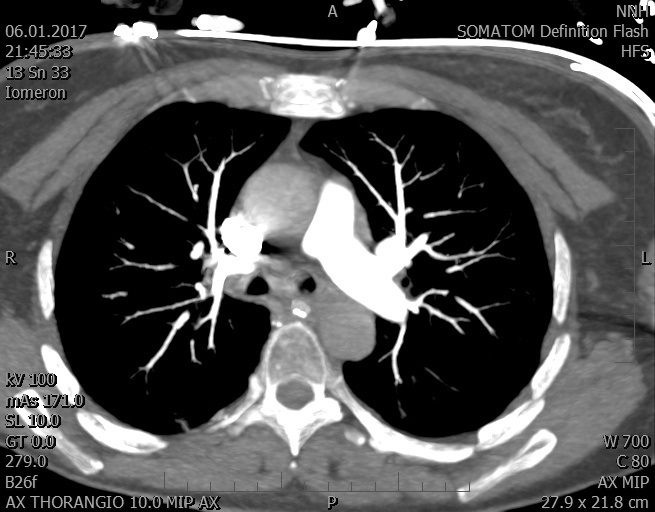

Video 1 - Akutní koronarografie prokázala normální nález na věnčitých tepnách s výjimkou suspekce na lehký spasmus na pravé koronární tepně.Echokardiograficky byla zjištěna těžká dysfunkce dilatované levé komory s nezvětšenou pravou komorou (video 2).

Video 2 - Echokardiograficky byla zjištěna těžká dysfunkce dilatační levé komory s nezvětšenou pravou komorou.Pro nejasnou příčinu zástavy jsme provedli i vyšetření výpočetní tomografií (CT), které vyloučilo plicní embolizaci (série 1 - soubory na konci článku). V den přijetí při přetrvávající oběhové nestabilitě byla nemocná opakovaně defibrilována pro fibrilaci komor se stabilizací rytmu po podání amiodaronu a mesocainu. Dle hemodynamických měření se jednalo o těžký kombinovaný šok. Vstupní laboratorní vyšetření bylo bez větších pozoruhodností. Posléze jsme doplnili anamnézu od příbuzných a zjistili, že pacientka užila do dvou hodin před srdeční zástavou první tabletu amoxicilinu na lehký respirační infekt. Při nevýtěžnosti vstupních vyšetření a nových anamnestických informacích jsme doplnili 14 hodin po kolapsu vyšetření koncentrace tryptázy v séru, která byla extrémně zvýšena (tabulka 2), což nás vedlo k podezření na anafylaxi.